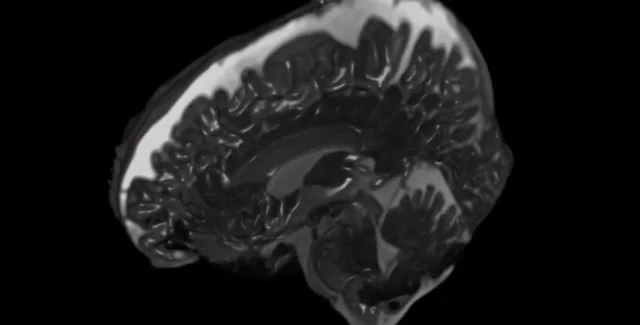

Фото: Courtesy of Stevens Institute of Technology

На видео видно, как мозг дрожит внутри черепа, когда кровь и другие жидкости протекают в нем.

В новых исследованиях ученые использовали метод сканирования мозга, который часто используется для захвата статических 2D-изображений органов, чтобы вместо этого создавать 3D-видео мозга, движущегося в реальном времени. Можно увидеть пульсирующую ткань мозга в ответ на прилив крови к кровеносным сосудам и спинномозговую жидкость, которая несет питательные вещества и смягчает мозг, протекая внутри и вокруг полых пространств в органе, сообщает Livescience.

Новые видео "увеличивают" эти действия в мозгу, подчеркивая движение, чтобы его можно было легко проанализировать. По этой причине новый метод получил название "3D увеличенная магнитно-резонансная томография" или 3D уМРТ.

"На самом деле, это очень небольшое движение, обычно от 0,002 дюйма до 0,015 дюйма (от 50 до 400 микрометров), с точки зрения того, насколько сильно деформируется ткань", — говорит Мехмет Курт, доцент кафедры машиностроения в Технологическом институте Стивенса в Нью-Джерси, профессор Медицинской школы Икана на горе Синай в Нью-Йорке.

Создание движений примерно в 25 раз больше позволило исследователям оценить это действие более подробно, с точностью отслеживая его направление и амплитуду.